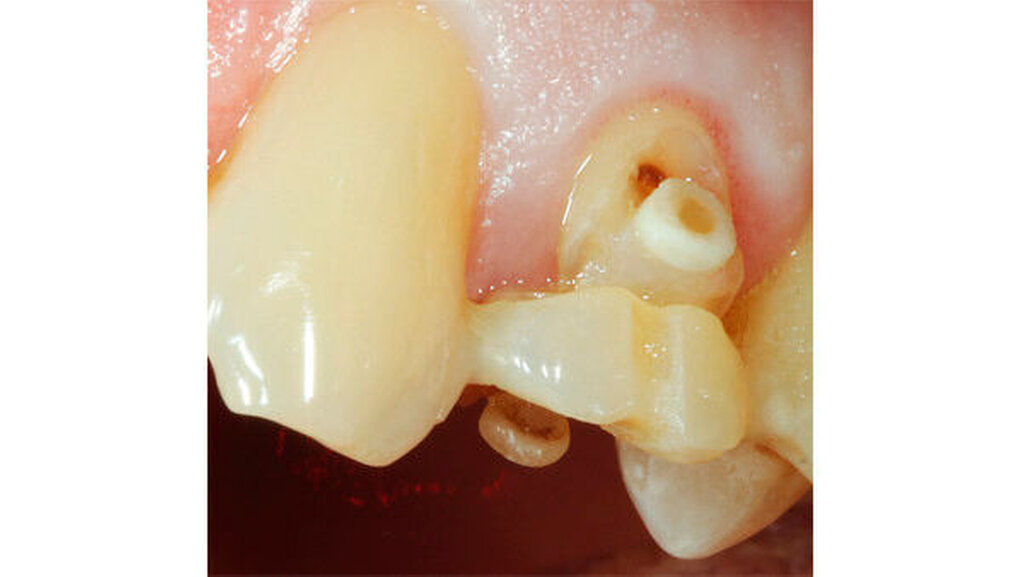

Nachdem im Rahmen einer Gesamtsanierung Zahn 21 nicht erhaltungswürdig gewesen ist, erfolgte eine forcierte Extrusion beginnend mit rund 700 cN mit zwei Gummiwechseln innerhalb von zwei Tagen und anschließend eine komplett noninvasive Entfernung des Zahnes.

Direkt unterhalb des Zahnhalses wurde eine etwa 2,5 bis 3 mm dicke Wurzelscheibe abgetrennt und genau an ihre ursprüngliche Stelle so replantiert, dass das umliegende Weichgewebe „wie gewohnt“ protektiv gestützt wurde (Abbildung 13). Die Vorhersagbarkeit dieser Methode konnte auch durch einen etwas außergewöhnlichen, weiteren Fall verifiziert werden: Entgegen unserer Vorgabe, sich etwa sechs Wochen nach der Replantation der Wurzelscheibe erneut vorzustellen, erschien die Patientin erst fünf Jahre später wieder in der Praxis und selbst nach diesem langen Zeitraum war der bukkale Knochen unter der replantierten Wurzelscheibe vollständig erhalten geblieben (Abbildung 14).

Im hier beschriebenen Fall des Zahnes 21 wurde über die replantierte Scheibe die provisorische Versorgung so erstellt beziehungsweise eingegliedert, dass die Scheibe in ihrer Position gesichert war und auch die Zunge (besonders in den ersten etwa 14 Tagen) selbige nicht mobilisieren konnte (Abbildung 15). Durch das gut erhaltene Parodont war die Wurzelscheibe nach diesem Zeitraum bindegewebig wieder eingewachsen.

Unter der replantierten Wurzelscheibe an Zahn 21 (Abbildung 16) erfolgte in nur acht Wochen eine vollständige Knochenregeneration der Alveole. Dabei blieb auch der bukkale Hart- und Weichgewebsanteil vollständig erhalten. Nach Entfernung der Scheibe war für eine optimale Positionierung des Implantats in allen Dimensionen ausreichend Knochen vorhanden (Abbildungen 17 und 18).

Ergebnis: Da nicht nur die bukkale Knochenwand mit dieser Methode vollständig erhalten werden konnte, sondern auch das periphere Weichgewebe gestützt wurde (Abbildung 19), konnte unter vollständigem Erhalt der Papillen mittels der eingegliederten Krone ein in jeder Hinsicht optimales Ergebnis erzielt werden. In der Nachsorge auch nach etwa fünf Jahren fügte sich die Versorgung funktionell und ästhetisch optimal ins Gesamtbild ein (Abbildung 20).